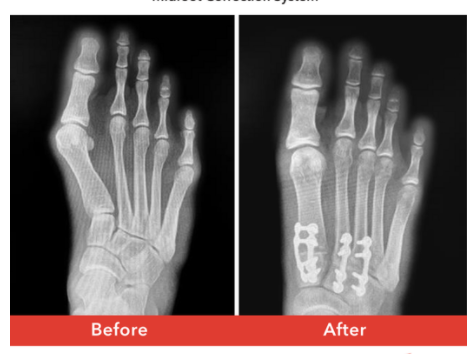

If you can do it freehand you should. That said. Not to quote some sort of company line. I feel like I've seen a lot of awful lapidus during my travels. The company's products, images, etc do at times show what we should be aiming for - that powerful correction can be produced (regardless of the system). You don't have to buy all of it, but a lot of historic lapidus is wildly under corrected and I think a lot of people may not have even realized what it should look like when they are done.

My 2nd month out of 4th year a resident proudly showed me their first lapidus. It was fused essentially wide open in situ at not kidding like ..40 degrees. The attending casually explained to the patient that it was their mistake to not explain to the patient before hand that she was always going to need two procedures and now it was time for her 1st MPJ. It was absurd. There was no initial correction. The 1st MPJ would theoretically resolve the great toe malposition but the patient wasn't going to benefit from the usual IM decrease caused by decompression because the 1st TMTJ position was fixed. I don't know what they were really thinking, but the resident was very clearly -proud- when he showed me the x-ray.